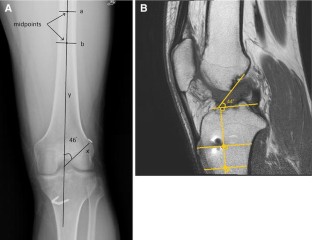

Fig. 3

5. Papannagari R, Gill PJ, Defrate LE, Moses JM, Petruska AJ, Li G (2006) In vivo kinematics of the knee after anterior cruciate ligament reconstruction: a clinical and functional evaluation. Am J Sports Med 34:2006–2012

24. lllingworth KD, Hensler D, Working ZM, Macalena JA, Tashman S, Fu FH (2011) A simple evaluation of anterior cruciate ligament femoral tunnel position: the inclination angle and femoral tunnel angle. Am J Sports Med 39:2611–2618